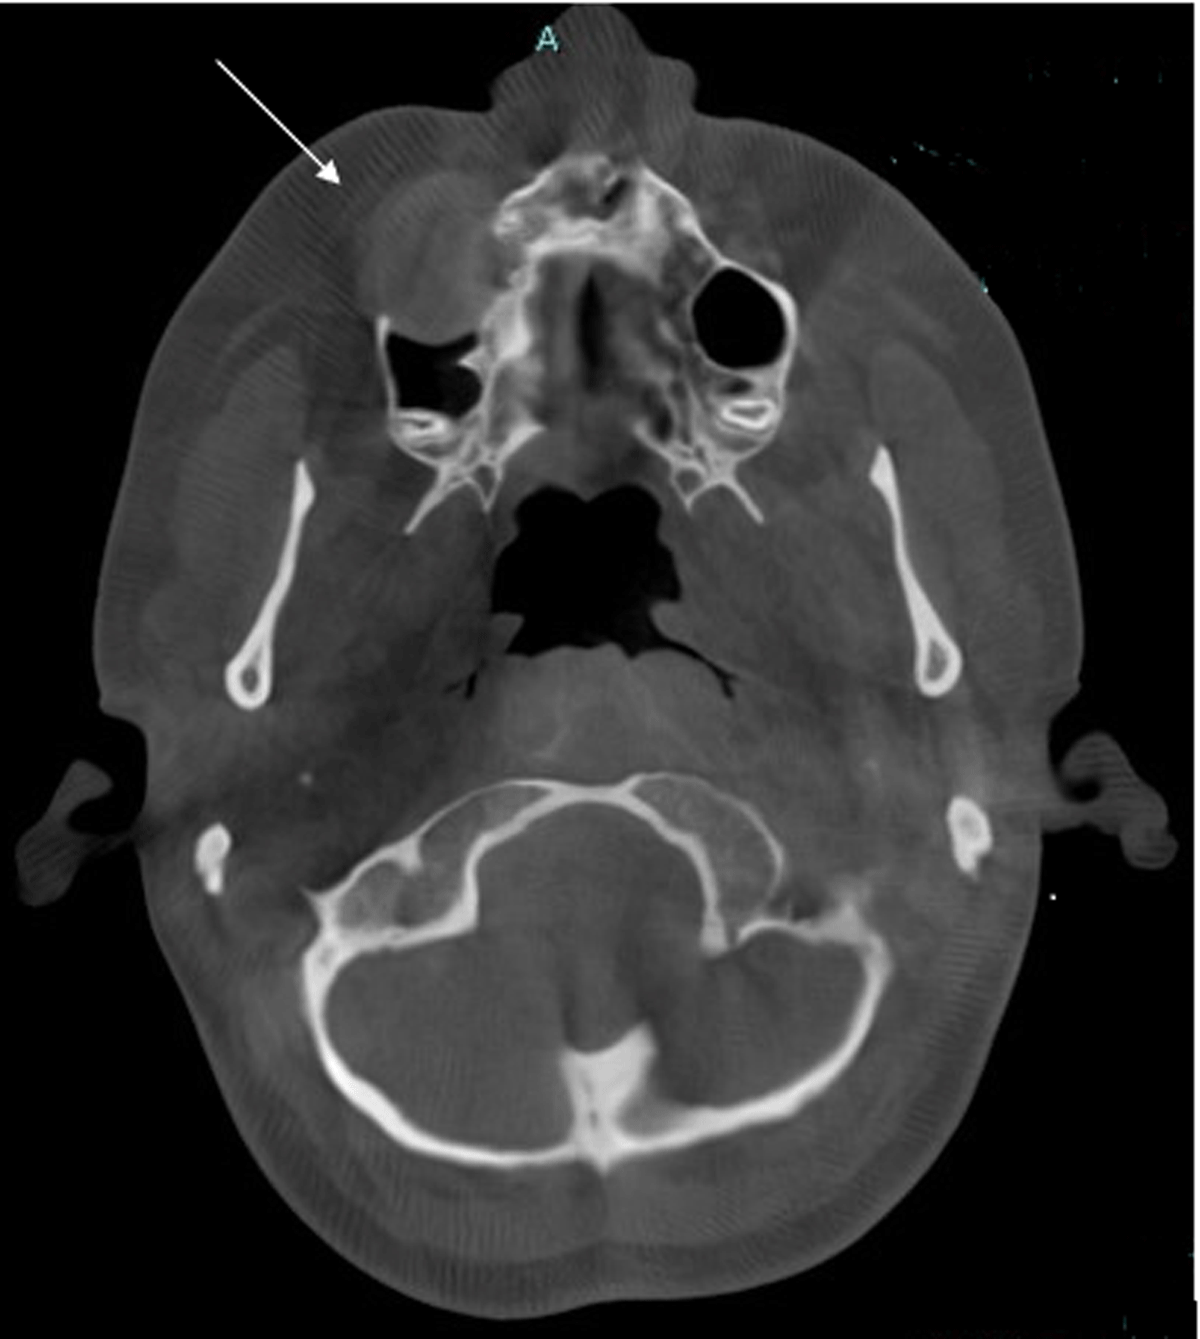

Cone-beam computed tomography (CBCT) scan showed a sharply demarcated hypodense nodule (2.1 cm) centred in the space between the roots of tooth element 14 and 15 (Figures 1 and 2).

Figure 1.